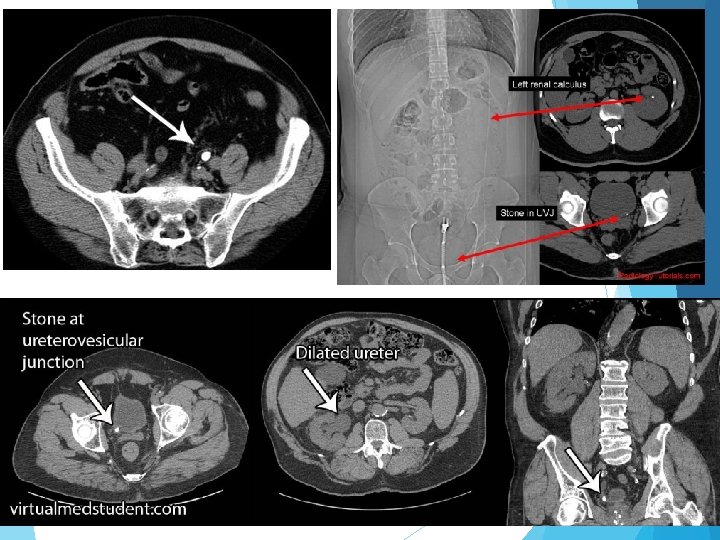

Direkt üriner sistem grafisi (DÜSG) Ultrasonografi İntravenöz pyelografi (IVP) Nükleer radyoloji Bilgisayarlı tomografi (Non kontrast Spiral BT)

BT BT’de hastalar daha az radyasyona maruz kalır ve kontrast ajan kullanılmaması avantajını sağlar. Bt’nin başka bir avantajı da ürik asit ve ksantin taşları gibi non-opak taşları da görüntüleyebilmesidir. Akut yan ağrısı olan hastalarda kontrastsız abdomen tomografi (NCCT), zaman içinde IVP’nin yerini almış ve standart yaklaşım haline gelmiştir NCCT, IVP ile karşılaştırıldığında daha yüksek sensitivite ve spesifite göstermektedir )%95 -97). BMI <30 olan hastalarda NCCT çekilecekse düşük doz NCCT çekilmesi önerilmektedir.

TAŞ SINIFLAMASI Boyut <5 mm, 5 -10 mm, 10 -20 mm, >20 mm Yer Üst, orta veya alt kalis Renal pelvis Üst veya alt üreter Radyoopasite Radyopak: Ca okzalat dihidrat, Ca okzalat monohidrat, Ca fosfat Zayıf radyopak: Mg amonyum fosfat, apatit, sistin Radyolüsen: ürik asit, amonyum ürat, ksantin, 2 -8 dihidroksiadenin, ilaç taşları